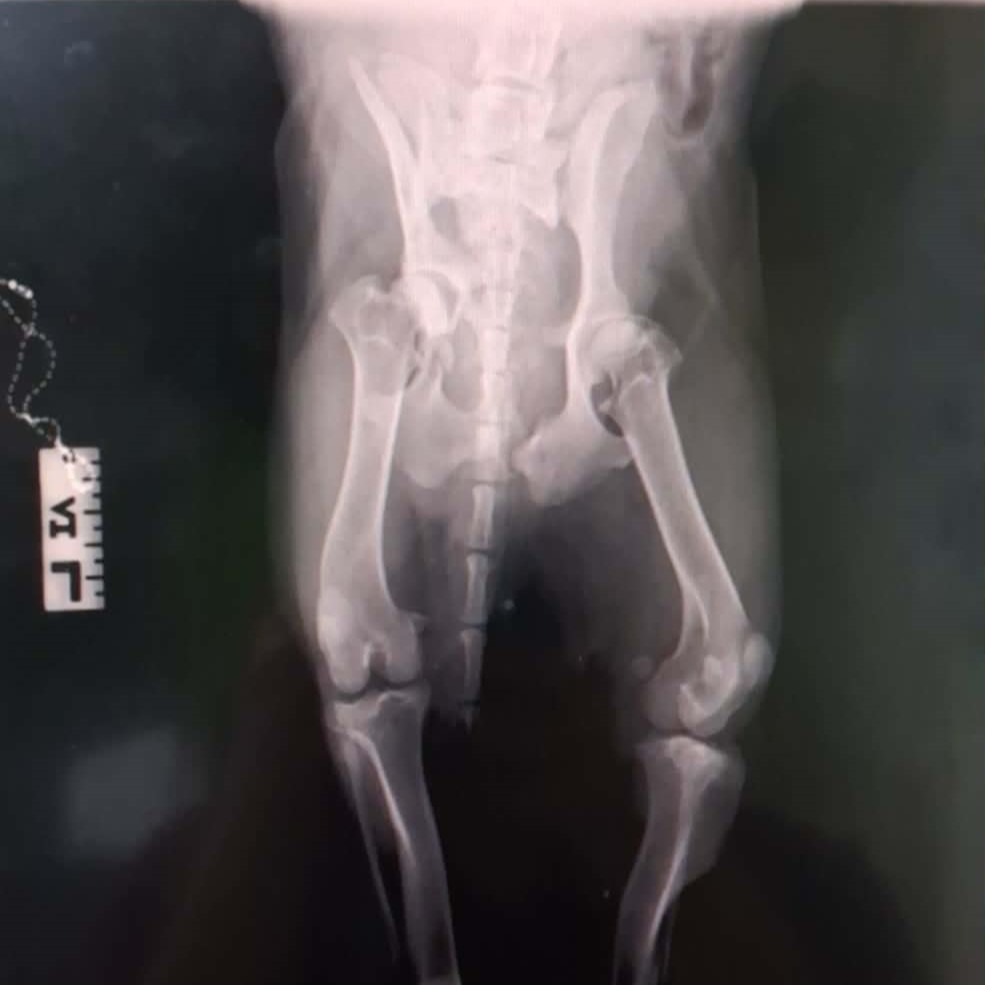

Geburtsdatum: ca. 09/2025

Aufenthaltsort: Griechenland / Karditsa

Notfellchen aufgrund von: schwerem Autounfall mit komplizierten Frakturen an mehreren Beinen